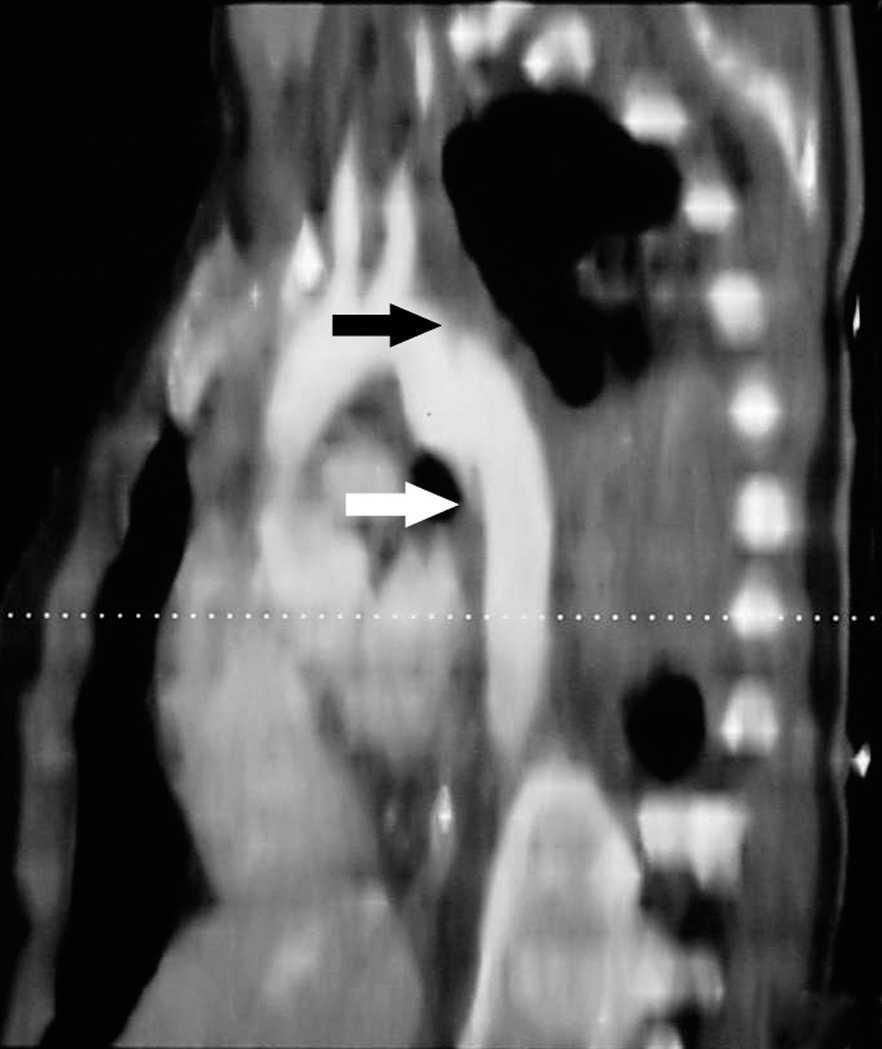

Mujer de 21 años sin antecedentes de interés que presenta politraumatismo tras accidente de tráfico. La paciente es recogida con Glasgow de 15 puntos precisando intubación y conexión a ventilación mecánica por insuficiencia respiratoria. En la tomografía axial computarizada (TAC) torácica de ingreso presenta contusión pulmonar bilateral (*1, fig. 1) y una imagen de "flap" intimal, a 2 cm de la salida de la arteria subclavia izquierda, de morfología irregular y con aumento de calibre compatible con rotura traumática de aorta torácica (*2, fig. 1). En la reconstrucción de la TAC también se aprecia dicha imagen de rotura traumática de aorta (fig. 2). Se procedió de manera urgente a la colocación por vía femoral de prótesis aórtica endovascular con buen resultado final.

Figura 1